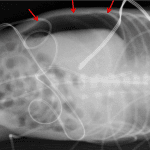

- Large volume pneumoperitoneum

- Featureless nondistended loops of bowel are seen throughout the abdomen

- Diffuse granular airspace opacities at the lung bases

- Umbilical venous catheter tip projects over the right atrium

- Umbilical arterial catheter tip projects at the level of T5-T6

- Pneumoperitoneum

Large volume pneumoperitoneum.

Featureless nondistended loops of bowel are seen throughout the abdomen without convincing pneumatosis.

Diffuse granular airspace opacities at the lung bases, which may relate to respiratory distress syndrome.

Umbilical venous catheter tip projects over the right atrium.

Umbilical arterial catheter tip projects at the level of T5-T6.

- Football sign – generalized hyperlucency of the abdomen with the falciform ligament resembling the lacing of a football

- Rigler’s sign – gas along bowel walls makes both the inner and outer margins of the wall visible

- Continuous appearance of the diaphragm (remember that pneumomediastinum can also do this)